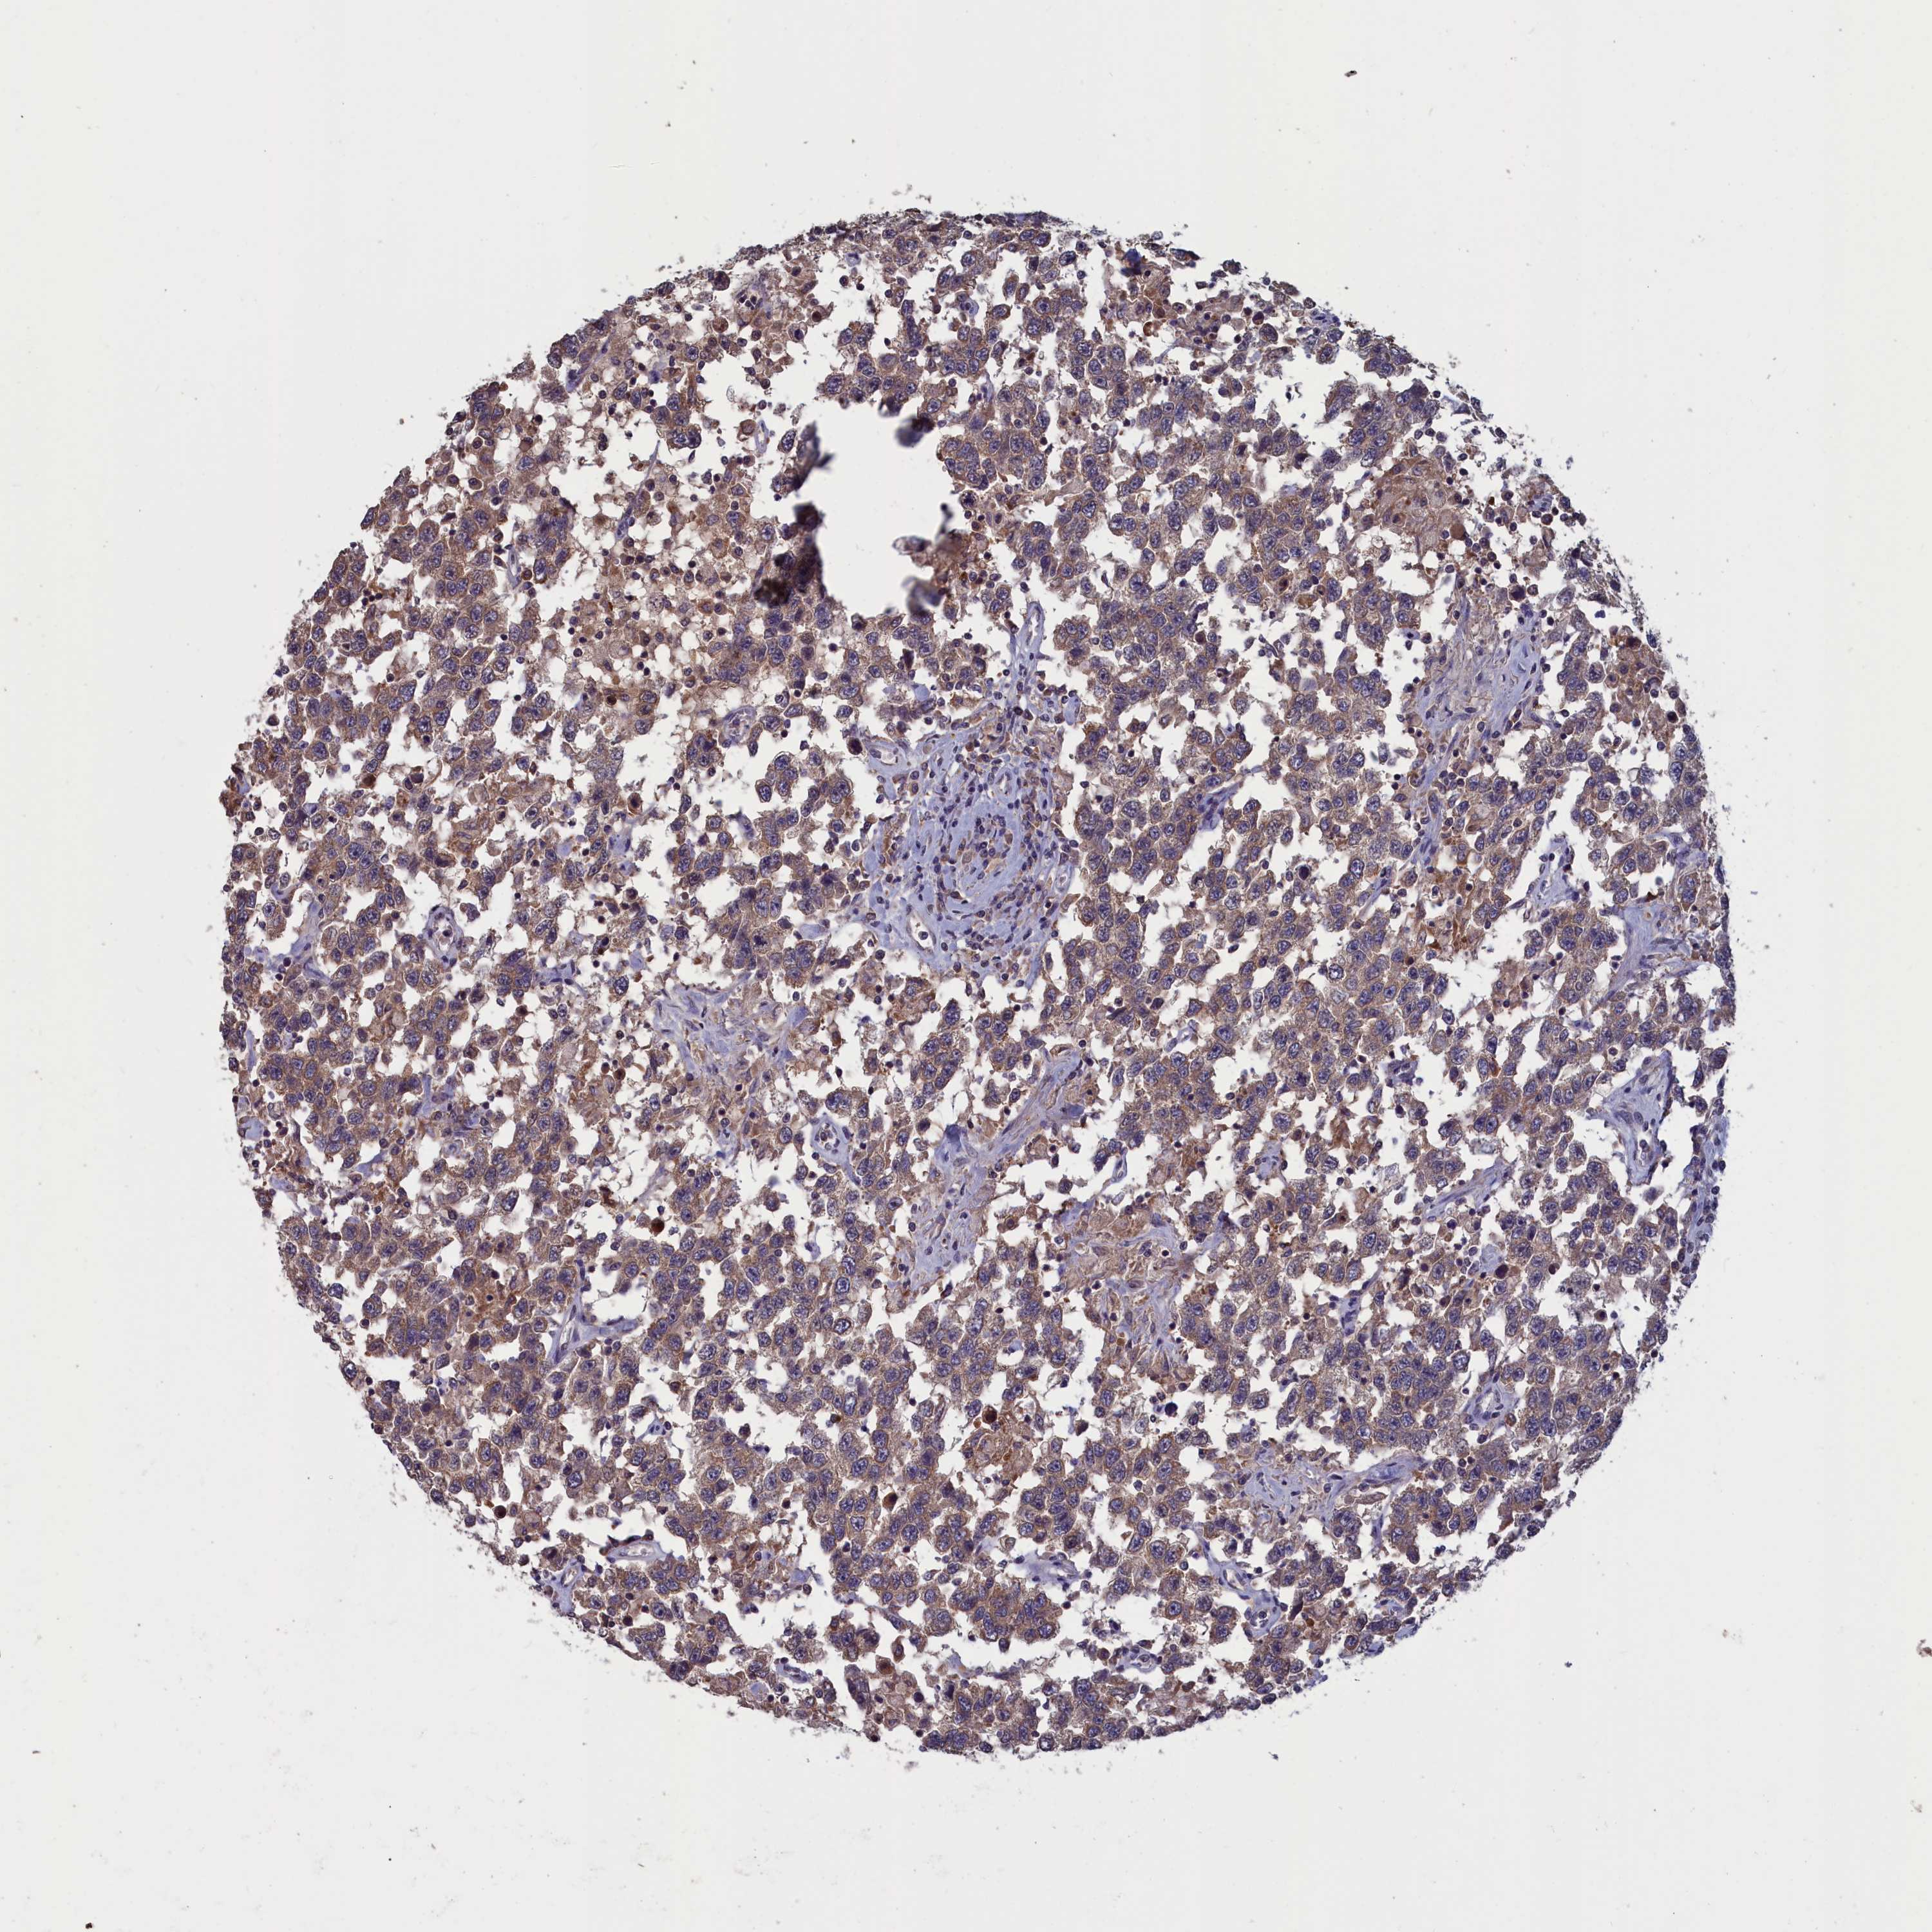

TESTIS CANCER - Protein expressioni

A mouse-over function shows sample information and annotation data. Click on an image to view it in a full screen mode. Samples can be filtered based on level of antibody staining by selecting one or several of the following categories: high, medium, low and not detected. The assay and annotation is described here.

Note that samples used for immunohistochemistry by the Human Protein Atlas do not correspond to samples in the TCGA dataset.

Antibody stainingi

Antibody staining in the annotated cell types in the current human tissue is reported as not detected, low, medium, or high, based on conventional immunohistochemistry profiling in selected tissues. This score is based on the combination of the staining intensity and fraction of stained cells.

Each image is clickable and will lead to virtual microscopy that enables deeper exploration of all samples and also displays staining intensity scores, fraction scores and subcellular localization as well as patient and tissue information for each sample.

Antibody HPA042504

Carcinoma, Embryonal, NOS

Seminoma, NOS